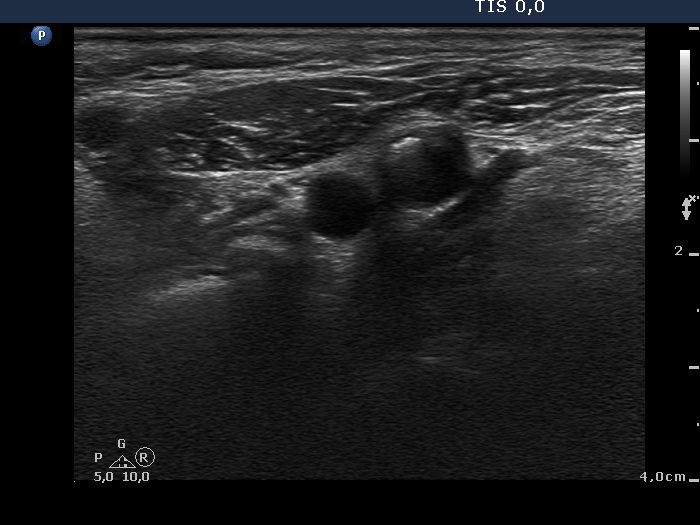

Lateral to the left lobe, transverse view. There is a node presenting microcalcifications.